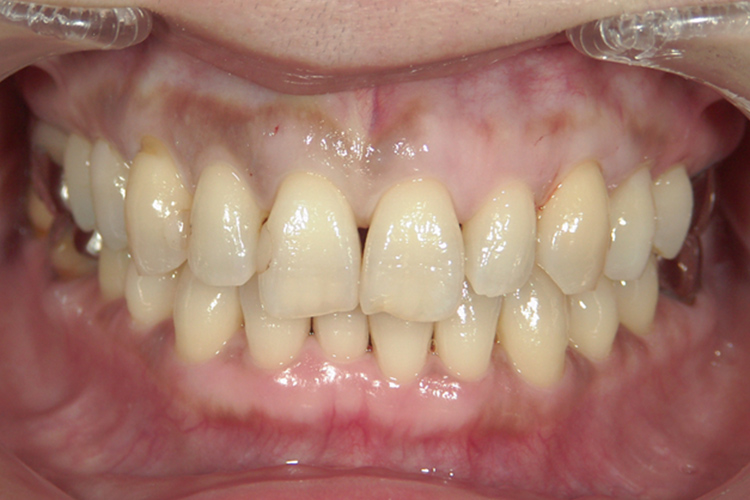

予防治療

歯周病は、歯の支えとなる部分の骨を溜まった汚れや歯石が溶かしてしまう病気です。

虫歯と並んで歯を失う原因の一つとなっている歯周病ですが、その治療にはプラーク(歯垢)を取り除き、歯肉、歯根膜などの歯周組織の炎症を抑えることが有効となっています。

原因を取り除くことで再発の予防もしていきます。

細菌を歯周ポケットから除去することで、歯周組織の健康は維持できますが一度歯周組織を失ってしまうと、自然に元に戻ることはありませんので適切な治療をすることが大切です。